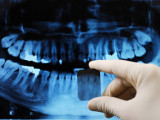

• panoramique ou orthopantomogramme, cette radiographie permet de visualiser la totalité de la bouche, d'une articulation à l'autre.

On distingue les radiographies argentiques ayant comme support un film et les radiographies numériques qui sont prises par un capteur numérique ou une plaque photosensible. L'image numérique est alors stockée dans un ordinateur.